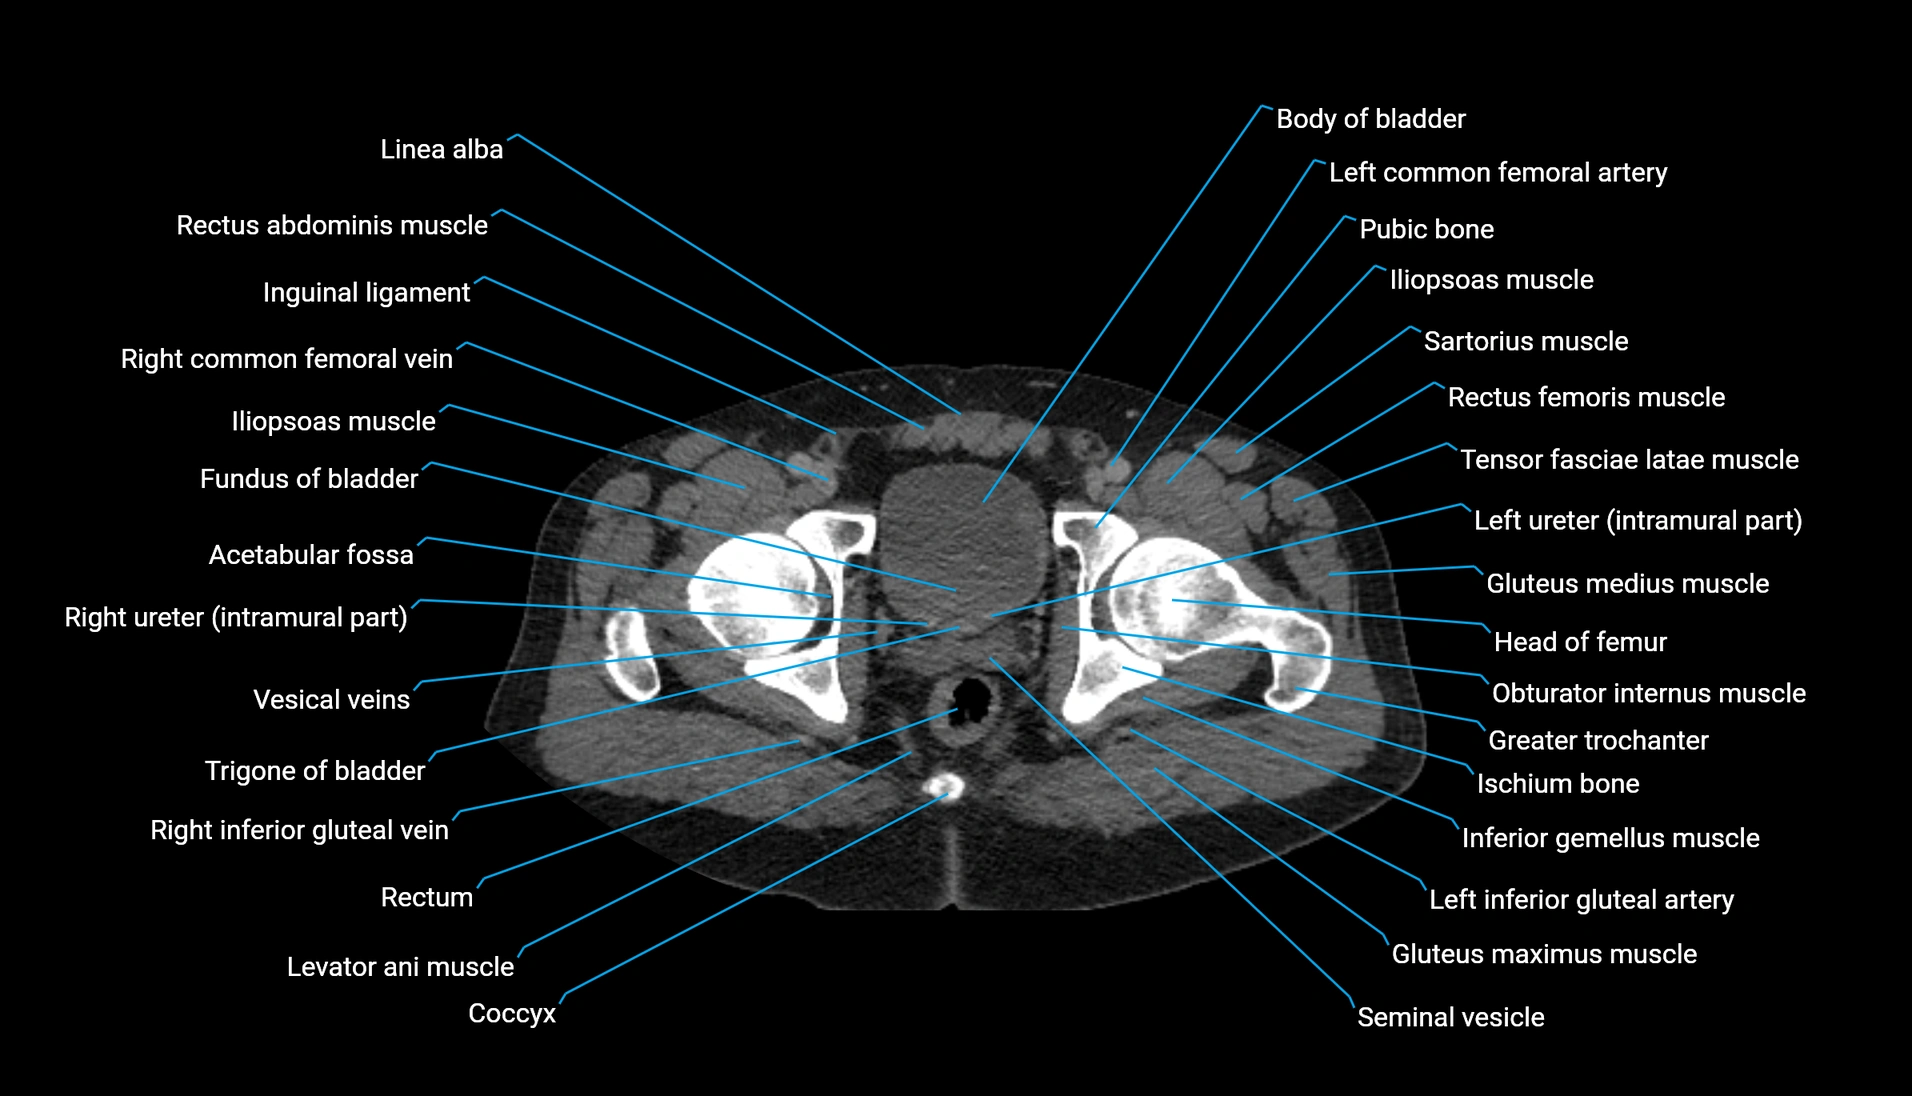

CT Appearance

Non-contrast CT:

-

Demonstrates cortical bone of acetabular rim in excellent detail

Detects fractures, dysplasia, retroversion, or bony overcoverage (pincer impingement)

3D reconstructions used in preoperative hip surgery planning

CT Post-Contrast (CT Arthrography):

Joint contrast outlines the acetabular labrum, cartilage, and margin

Demonstrates labral tears, cartilage defects, and subtle bony abnormalities

Alternative to MR arthrography in patients with MRI contraindications

CT VRT 3D image

CT image